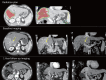

Background: Hepatocellular carcinoma (HCC) remains a major health issue because of its increasing incidence and because of the complexity of its management. In addition to the traditional potentially curative treatments, i.e., liver transplantation and surgical resection, other new and emerging local therapies have been applied with promising results.

Summary: Radiotherapy (RT) and interstitial treatments, such as radiofrequency ablation (RFA), microwave ablation (MWA), and irreversible electroporation (IRE), have recently opened new and interesting treatment scenarios for HCC and are associated with promising results in selected patients. Herein, we describe the emerging role of interventional oncology for the treatment of HCC and focus on the different Western and Eastern approaches.